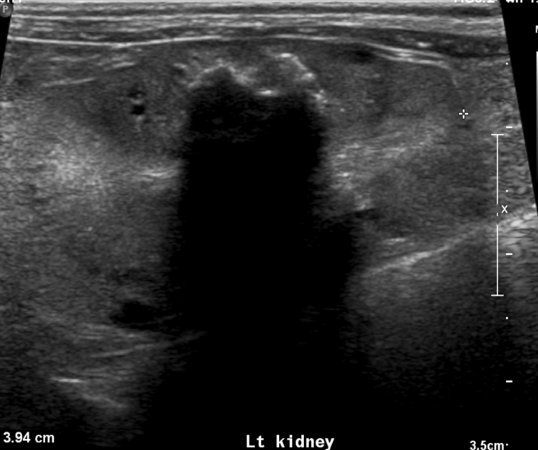

enlarged smooth kidneys with distended pelvis ± distended ureters

hydronephrosis